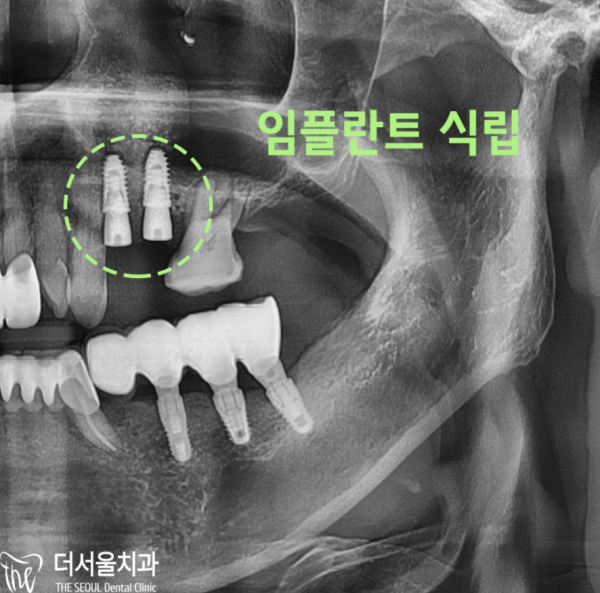

계획대로 임플란트가 잘 마무리되었습니다.

사실 이 환자분은 저희 모란역 더서울치과를 찾아오시기 전에

다른 곳에 가셨는데, 치료가 어렵다는 말씀을 듣고 저희 치과를 찾아오셨습니다.

저희도 실제로 치료를 하면서 많은 걱정을 하고 치료를 하게되었습니다.

치조골이 거의 없는 상태의 환자분들은 뼈이식을 한 후에 픽스쳐를 심게됩니다.

치료에 필요한 시간도 오래 걸리는 고난도의 케이스입니다.

The implant was finished well as planned.

Actually, before this patient visits The Seoul Dental Clinic at Moran Station

He went somewhere else, but he came to our dentist because he heard it was difficult to treat.

As we were actually doing the treatment, we worried a lot and got to do the treatment.

Patients with little alveolar bone are implanted after bone transplantation.

It is a high-level case that takes a long time to treat.